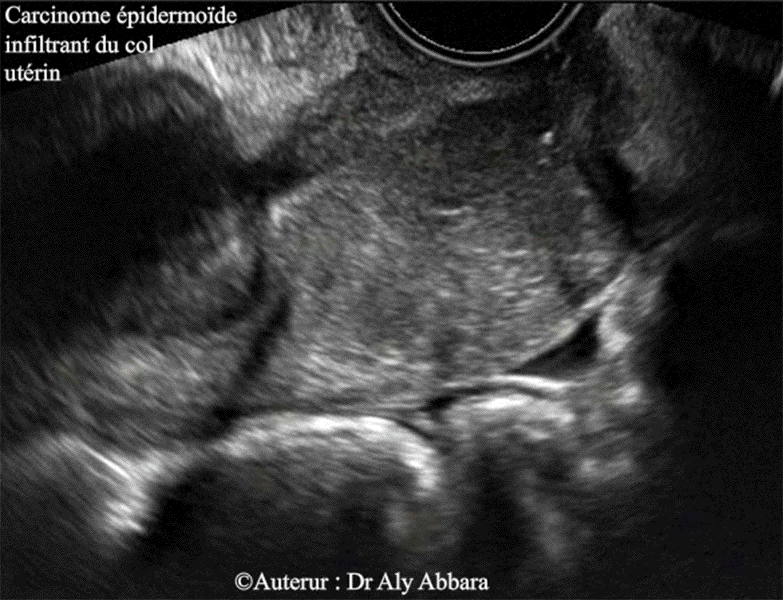

Carcinome épidermoïde infiltrant du col utérin

• L'aspect échographique d'un carcinome épidermoïde invasif, infiltrant du col utérin ; il s'agit d'un processus tumoral évoluant principalement au sein des structures internes du col.

• A l'échographie par voie endovaginale :

• La coupe sagittale montre la présence :

• d'une hématométrie (estimée à 15 ml) ;

• d'un processus tumoral hétéroéchogène évoluant principalement au sein de la paroi postérieure du col utérin, puis partiellement dans sa paroi antérieure.

• Les deux mode Doppler (Doppler energy et Dynamic flow) montrent qu'il s'agit d'une structure tissulaire hypervascularisée.

• Les biopsies de l'ulcération exocervicale, et le curetage de l'endocol confirme le diagnostic de carcinome épidermoïde infiltrant, bien différencié, du col utérin.